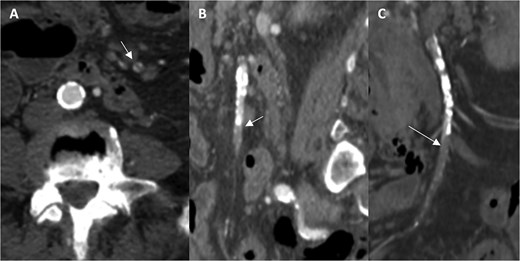

A 76-year-old female patient with a medical history of diabetes mellitus and cholecystectomy presented to the emergency department with a 7-month history of postprandial abdominal pain, food fear, and weight loss (25–30 kg). Over the past 3 days she referred symptom worsening to constant pain. On the physical examination, the abdomen was tender to palpation. Laboratory results revealed leukocytosis (13.700/μl), high C-reactive protein (23 mg/dl) and lactate 0.7 mmol/L. A previously performed computed tomography angiography (CTA) in context of a lithiasic cholecystitis revealed celiac trunk occlusion and pre-occlusive stenosis of the SMA ostium but the patient was not referred for a vascular surgery consultation. A CTA scan obtained in the emergency department revealed thrombotic occlusion of the SMA origin associated with distal embolization (Fig. 1A–C). In this context, the diagnosis of acute-on-chronic mesenteric ischemia was assumed, and the patient was proposed for urgent endovascular revascularization. A 7F (French) sheath was placed via percutaneous access in the left brachial artery, and SMA catheterization was performed using a triaxial system (sheath, MP catheter and Progreat® catheter). Diagnostic angiography confirmed the CT findings (Fig. 2A). Catheter-directed thrombolysis was first performed with a 5 ml bolus of alteplase, followed by percutaneous thrombectomy using the Penumbra® system (Fig. 2B), with retrieval of fresh thrombus (Fig. 3). Primary stenting of the SMA ostium was also performed using an Advanta® 6 × 39 mm stent with proximal flair, with an excellent imagological result (Fig. 4A and B). The postoperative course was uneventful, with significant improvement of symptoms and clinical status. A CTA prior to discharge revealed a patent stent with proper placement and no evidence of residual thrombus (Fig. 5A and B). The patient was discharged on the seventh postoperative day with apixaban 5 mg twice daily. Follow-up of the patient at 6 months revealed that the stent remained patent, with no reported abdominal complaints. The patient gained 15 kg at this point of follow-up.

Angiographic images before (A) and after (B) primary stenting of SMA ostium using a 6 × 39 mm Advanta® stent with proximal flare.